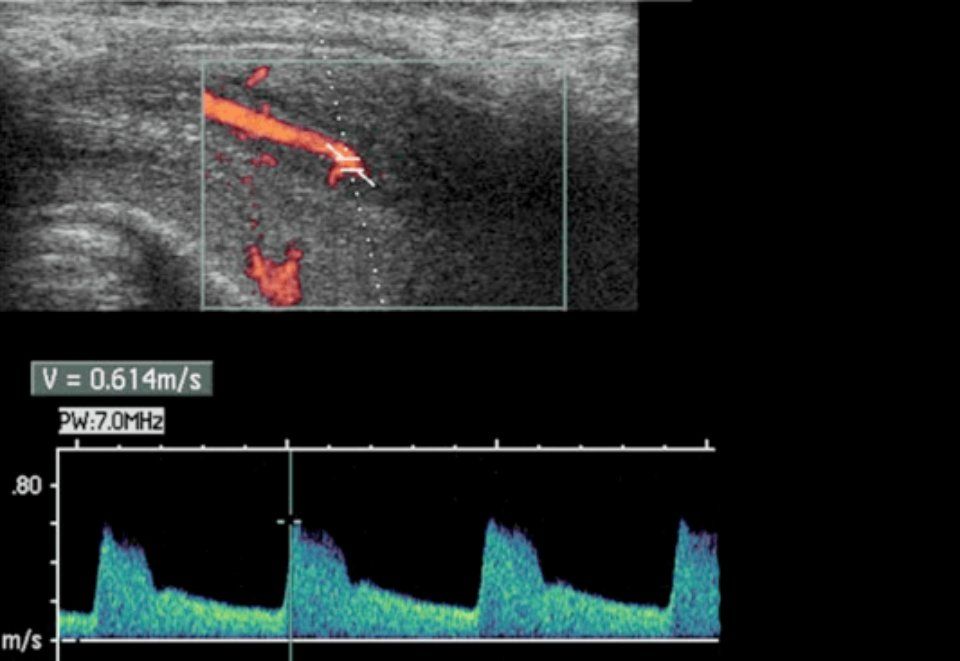

Tra gli esami di secondo livello attualmente è considerato “gold standard” per porre diagnosi di certezza di DE l’Eco-color-Doppler dinamico del pene (FIGURA 2), indicato per la valutazione dell’integrità vascolare del pene. Si tratta di uno studio dinamico, ossia funzionale, eseguito in condizioni di base e dopo stimolazione con farmaci iniettati all’interno del pene, per studiare l’afflusso ed il deflusso del sangue in condizione di erezione indotta farmacologicamente mediante sostanze vaso-attivo a dosaggio standardizzato (Alprostadil).

2 Ecodoppler Dinamico

2b: Misurazione doppler del flusso arterioso

il flusso arterioso dell’arteria dorsale del pene viene identificato all’ecografia e l’ampiezza del flusso viene misurata mediante l’effetto doppler.